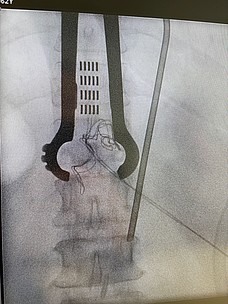

Vor allem bei bestimmten Schmerzsyndromen, die nicht oder nicht mehr ausreichend auf eine medikamentöse Therapie ansprechen, ist es möglich, durch die Rückenmarksstimulation eine Schmerzlinderung zu erzielen. Hierbei werden feine Elektroden in den Rückenmarkskanal eingesetzt, die elektrische Impulse abgeben. Das Einbringen der Elektroden kann in örtlicher Betäubung erfolgen. Die Elektroden werden durch einen Impulsgeber angesteuert, der unter die Haut am Gesäß oder an der Bauchwand der Patient:innen implantiert wird. Die abgegebenen elektrischen Impulse hemmen die Schmerzweiterleitung. Die Schmerztherapie durch Rückenmarksstimulation findet Anwendung nach Verletzung von Nerven oder des Rückenmarkes, aber auch bei Phantomschmerzen und bei behandlungsresistenten Schmerzen durch Durchblutungsstörungen bei Herzkrankheit (Angina Pectoris) und Gefäßkrankheit der Beine (pAVK). Bei der Gefäßkrankheit der Beine (pAVK) kann die Stimulation zudem dazu beitragen, die Durchblutung wieder zu verbessern und die Gliedmaßen zu erhalten. Die Nervenstrukturen bleiben bei der Rückenmarksstimulation erhalten, sodass die Stimulation jederzeit rückgängig gemacht werden kann. Die Einstellungen des Impulsgebers lassen sich von außen – auch durch die Patient:innen – verändern, sodass die Stimulation jederzeit an die Bedürfnisse der Patient:innen angepasst werden kann.